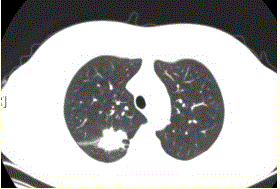

问题 患者女,54岁,无症状,常规体检透视时发现右上肺阴影。既往无结核病史。体格检查阴性。CT结果如下图。 本病例可见的征象包括

选项 A.分叶征 B.毛刺征 C.胸膜凹陷征 D.空泡征 E.含气支气管征 F.钙化

答案 ABCE